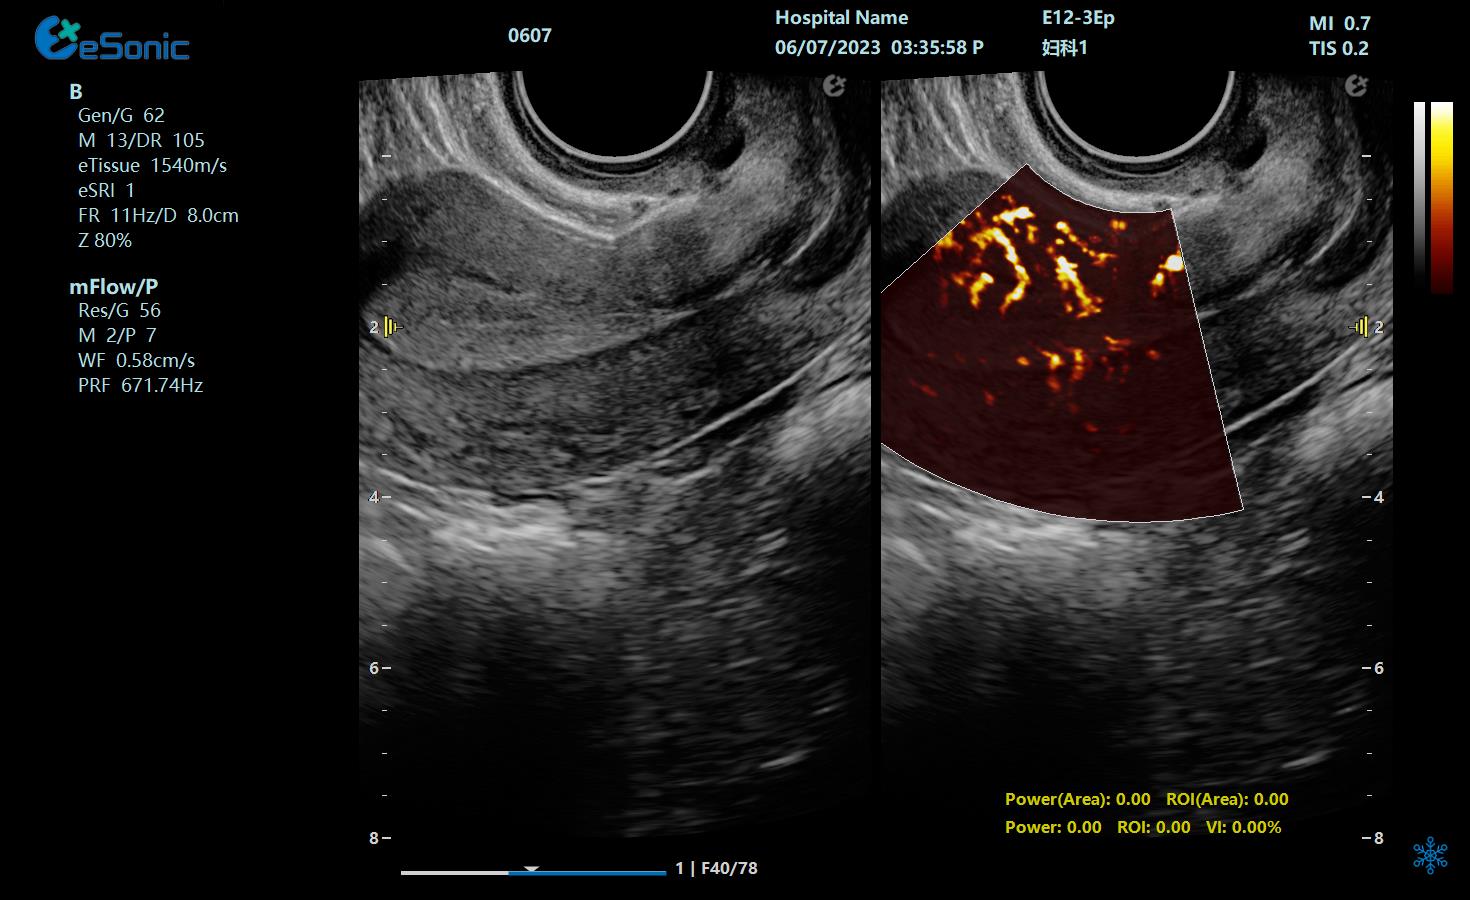

子宫内膜下螺旋动脉